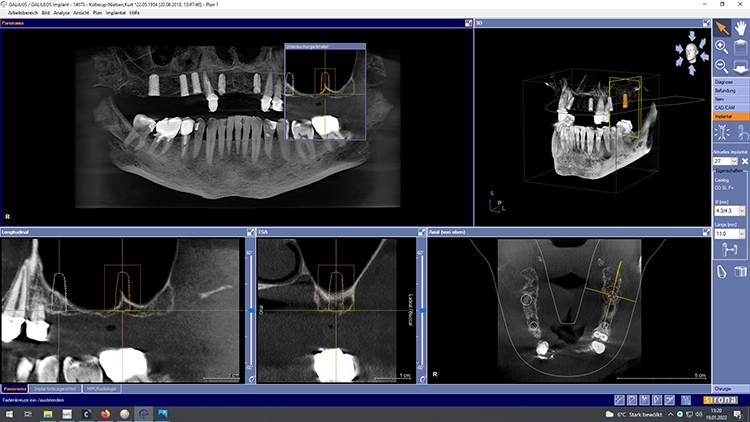

Der Therapieplan wurde in Abstimmung mit dem Patienten erstellt. Dabei war zu berücksichtigen, dass der Patient über den gesamten Behandlungszeitraum bis zur Fertigstellung der definitiven Restauration unbedingt kaufunktionell versorgt zu bleiben wünschte, da er zwischenzeitlich in Campingurlaub gehen wollte. Aufgrund der starken Pneumatisation der Kieferhöhlen wurden im posterioren Bereich beidseitig ein externer Sinuslift und nach Ausheilung der Strukturen die Implantation von sieben Implantaten (Conelog, Camlog, Wimsheim) mit unterschiedlichem Durchmesser und je 13 mm Länge geplant.

Die Implantatmaße und -positionen sowie der Umfang der Sinusbodenelevation wurden dabei in Sinne eines „backward planning“ anhand von DVT-Aufnahmen bestimmt. Zahn 13 sollte noch vorübergehend erhalten bleiben, um zusammen mit den bleibenden Zähnen 23 und dem entsprechend kariesbehandelten Zahn 24 bis zur Fertigstellung der definitiven Restauration der alten Teleskopprothese als Interimsersatz Halt zu geben. Als definitive Versorgung wurden drei VMK-Brücken auf NEM-Gerüsten vorgesehen. Damit sollte auch die natürliche Bezahnung im Unterkiefer von 37 bis 47 abgestützt werden.

Nach einer – aufgrund eines Campingurlaubs von sechs auf acht Monaten – verlängerten Heilphase konnte der Patient implantiert werden. In der Röntgenkontrollaufnahme zeigten sich stabile knöcherne Strukturen in den augmentierten Bereichen des Sinus. Die Insertionen erfolgte gemäß Protokoll frei Hand auf Grundlage der DVT-Aufnahme und orientiert an der alten Teleskopprothese.